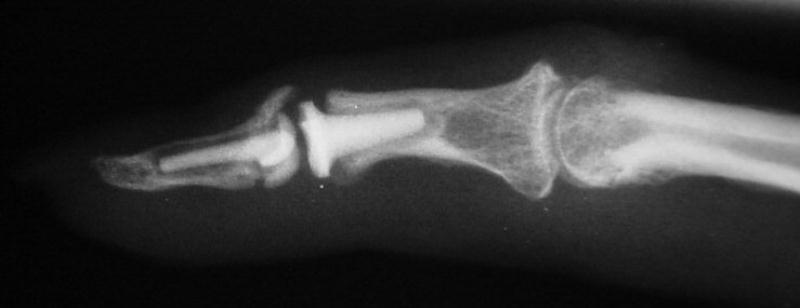

Intraoperative fluoroscopy.

The trial implant sizer shows the true size of the implant. The final implant has a radiolucent coating  which makes it appear smaller than it is on Xray.

Final implant radiographs.